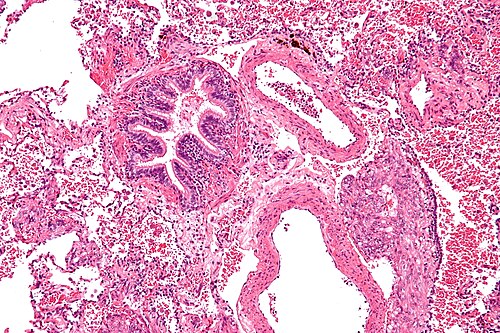

Intermediate magnification

Intermediate magnification. H&E stain.